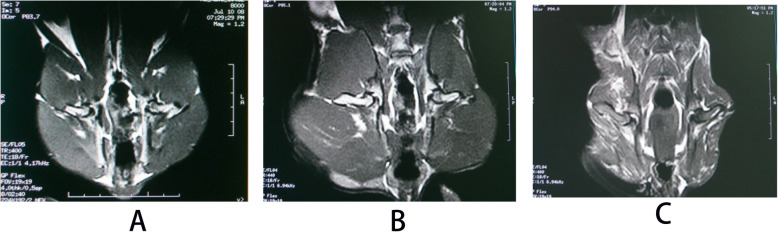

In the control group, the signal of femoral head was normal, and there was no abnormality inside and outside the joint soft tissue (Fig. 10a). In the model group, the bilateral femoral heads slightly got collapsed and flattened. The intensity of T2WI showed heterogeneous high-signal intensity. There were increasing hydrops in the right articular cavity and the gap of bilateral hip joints were uneven. The hydrops of bilateral spatium inter muscle are increased and there were rich hydrops in subcutaneous soft tissue (Fig. 10b). In the drug group, there were no apparent signals in bilateral femoral head and soft tissue muscle were noted. The gap of bilateral hip joints were equilate. There were a little hydrops in right articular cavity (Fig. 10c).

Fig. 10.

MRI (T2WI) of bilateral femoral heads of rabbits in three groups. a Control group, b model group, and c drug group